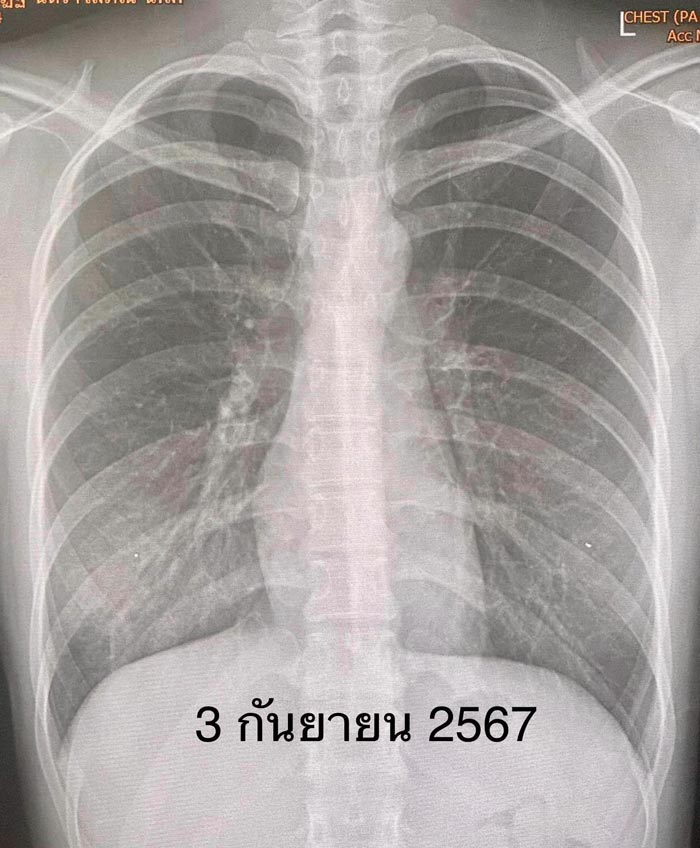

ตรวจร่างกาย มีไข้สูง 40.5 องศาเซลเซียส ระดับออกซิเจน 98% ฟังปอดปกติ เอกซเรย์ปอดมีฝ้าขาวที่ปอดข้างขวาด้านล่าง (ดูรูป) แยงจมูกส่งตรวจ PCR รหัสพันธุกรรม 22 สายพันธุ์พบเชื้อแบคทีเรีย Mycoplasma pneumoniae (ดูรูป) เจาะเลือดเม็ดเลือดขาวปกติ